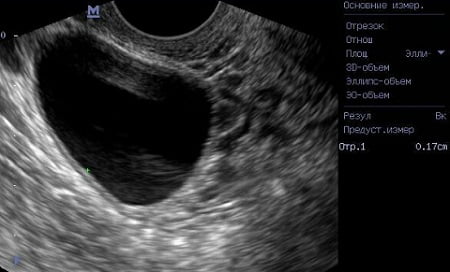

Диагностирование данного вида кисты выполняется на основании данных влагалищно-брюшностеночного исследования, лапароскопии и эхографии.

Во время гинекологического обследования кпереди и сбоку от матки обнаруживается округлая опухоль тугоэластической консистенции с гладкой поверхностью. При ультразвуковом исследовании определяется однокамерное шаровидное образование 3-8 см в диаметре с анэхогенным однородным содержимым. При выполнении допплерометрии обнаруживаются расположенные по периферии области кровотока с невысокой скоростью.